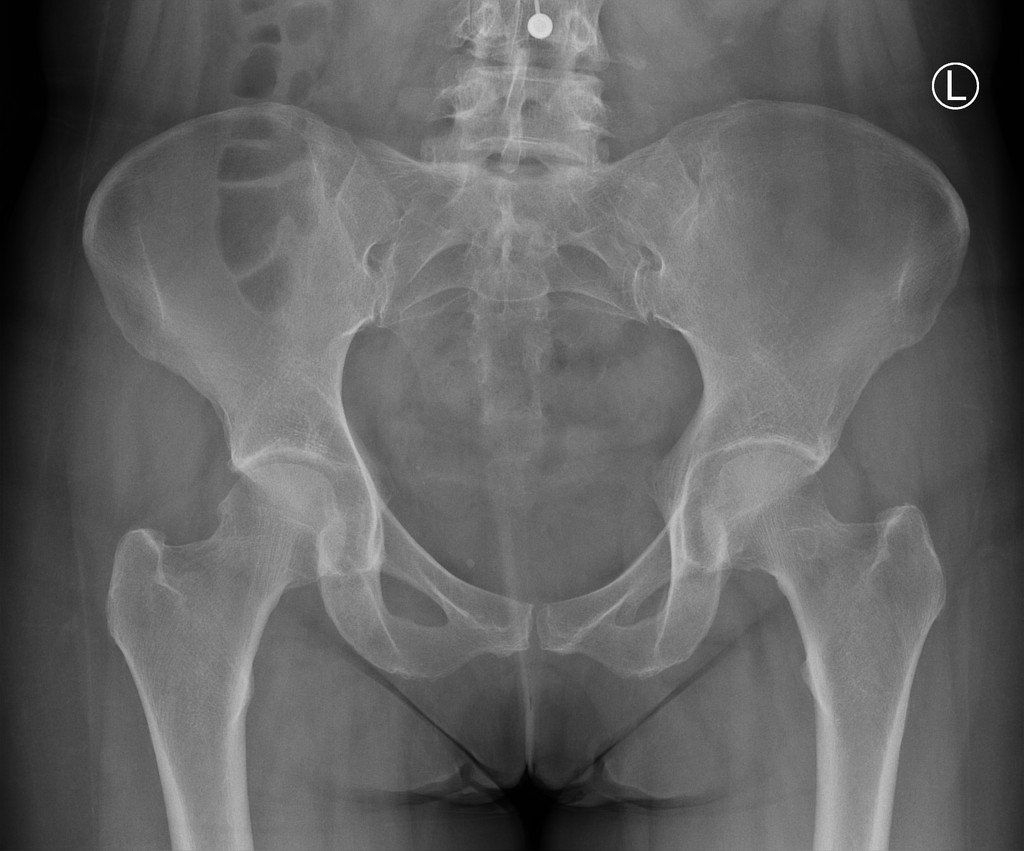

A total hip replacement is an extremely common orthopaedic procedure which provides positive outcomes for those experiencing pain and reduced function following end-stage degenerative hip osteoarthritis, rheumatoid arthritis or avascular necrosis of the femoral head.

During this procedure the head of the femur is replaced with a prosthetic head on the shaft whole the acetabulum (the ‘socket’) part of the hip is lined with a bowl shaped synthetic joint surface.

It is important to screen other joints such as the lumbar spine as this can also refer to the hip in some instance. Your surgeon may also request further imaging in the form of an x-ray to assess articular surface of the hip joint.